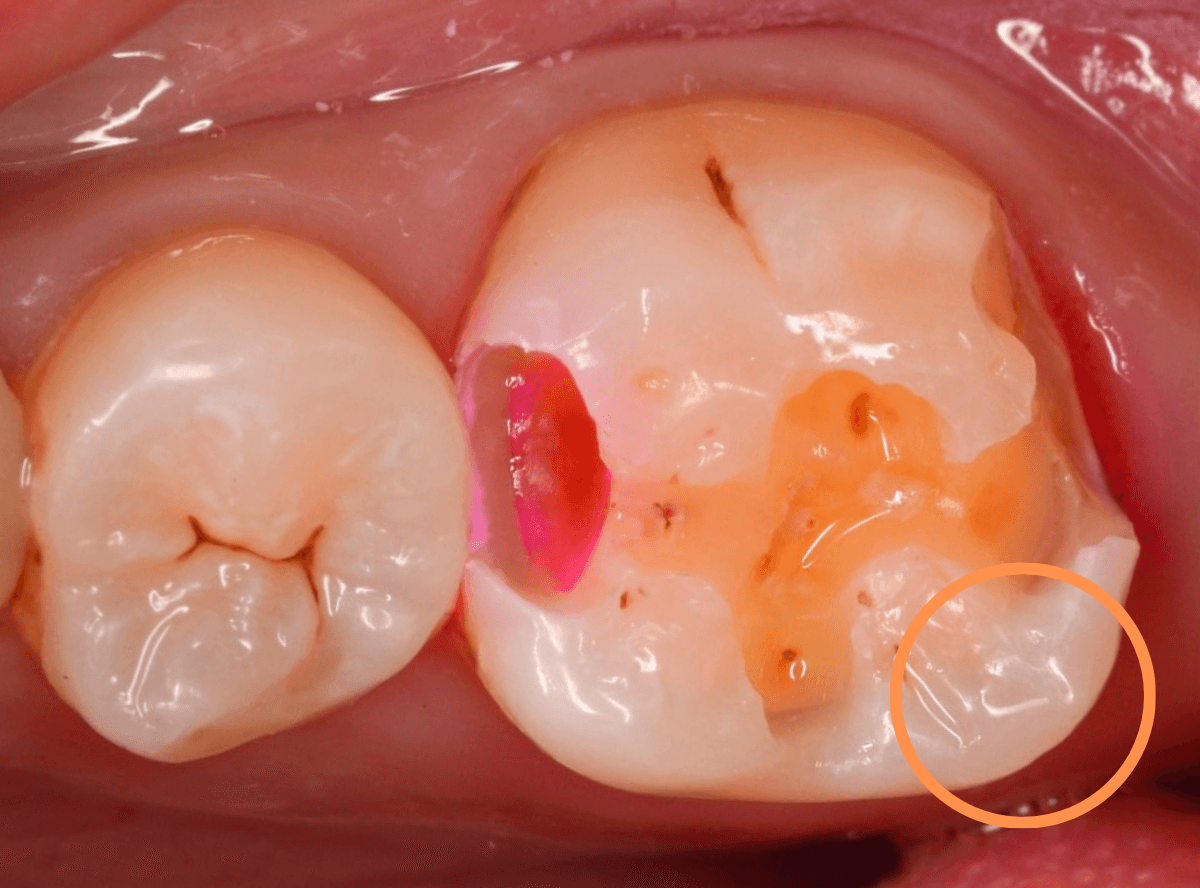

Case.23 歯のすきまから両側が大きな虫歯

「下の奥歯が痛む」という訴えで来院された患者さんのケースです。

目視でも、手前の奥歯がかけていて、中で虫歯が広がってるであろうことは予想できます。

ピンセットで歯を叩いてみても、手前の奥歯が痛むようです。

レントゲン写真で確認します。

青い線が神経、赤い線が虫歯の範囲です。

奥歯の方がより深い虫歯に見えますが、再度打診で確認したところ、やはり手前の奥歯が痛むそうです。

状況から、まず手前の奥歯から治療となりました。

麻酔をして、手前の奥歯のレジンを慎重に外します。

前に虫歯の治療をした時点で、神経スレスレの状態でしたので、削りすぎないように慎重にレジンを外さなければいけません。

レジンを外して、う蝕検知液で確認します。

レジンの中で虫歯が進行していたのがわかります。

慎重に全ての虫歯を除去しました。

何とか、神経が露出せずに済んでいます。

お薬をつめて、セメントで蓋をして経過観察します。

後日、状況を確認したところ、虫歯処置した後も、手前の奥歯が痛むとの事でした。

「我慢できないほどでもない」との事でしたので、引き続き経過観察しつつ、奥歯の治療を治療する事になりました。

奥歯は、レントゲンで見た通り、少し歯を削るとすぐに虫歯の穴が出てきました。

こちらは、ある程度虫歯を取ったところで染め出してみると真っ赤です。

ですが、何とか神経に達する前に、全ての虫歯を除去できました。

神経の治療が必要かと思っていたので、その点は幸運でした。

奥歯もお薬をつめて、セメントで蓋をして経過観察です。

何とか神経を取らずに済ませたいですが、どうなる事か・・・。